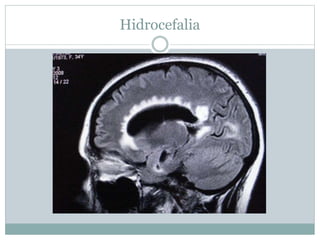

TAC- hidrocefalia

TAC hidrocefalia

Hidrocefalia